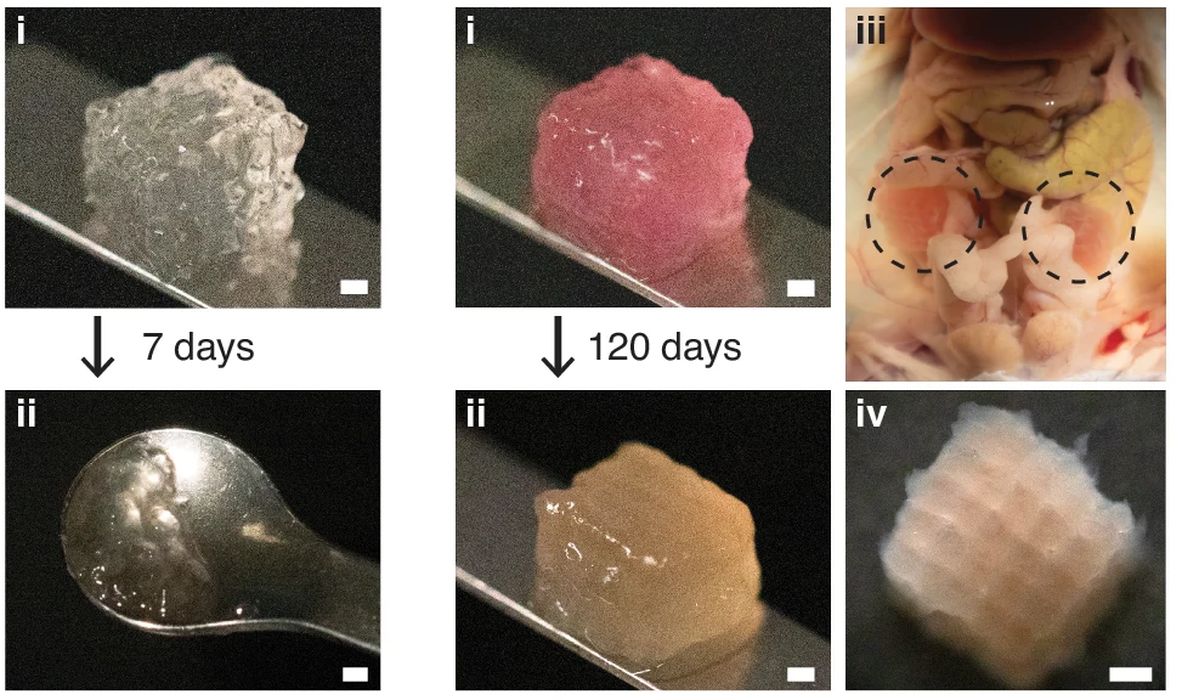

Major Problem Solved in Bioprinting: New Composite Scaffolds Show Promising Results

Researchers seem to have solved a major problem in bioprinting.